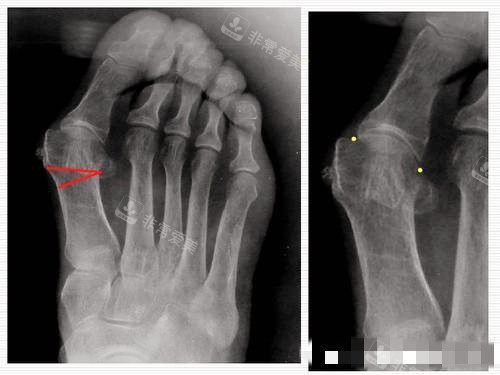

大脚骨X光片图片

虹桥医院拇外翻专科配备了一系列较高的医疗设备,如高精度的足部影像诊断设备,能够清晰地显示足部的骨骼结构和病变情况,为医生的诊断和治疗提供更准的依据。